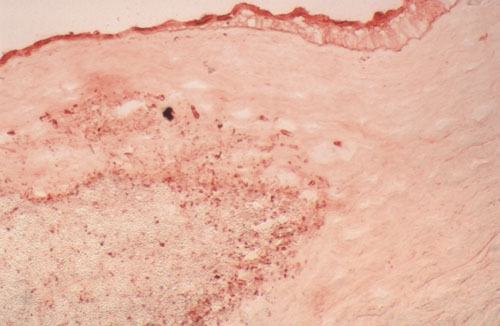

Figure 1. Cryosection of corneal tissue infected by Candida albicans

Cryosection of corneal tissue infected by Candida albicans (WGA, 5 mg/ml). Some yeast and pseudohyphae are stained in red, some yeast in the center of the abscess remain unstained. Corneal epithelium staining was noted (x20).